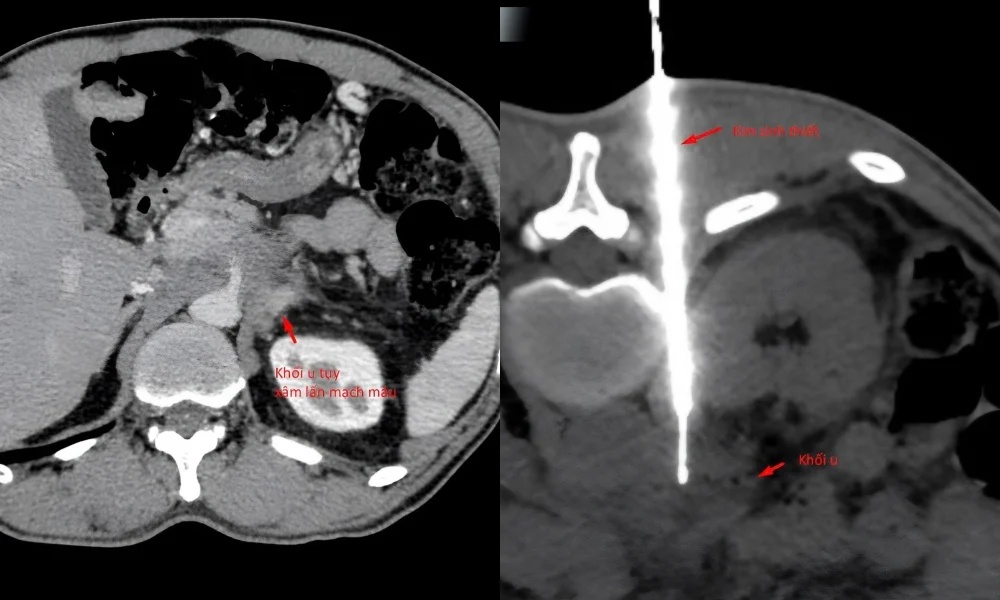

Theo Ths.BS Trần Văn Giang, Phó Giám đốc Trung tâm Chẩn đoán hình ảnh và Điện quang can thiệp Quốc tế, bệnh nhân được phát hiện có khối u tụy xâm lấn mạch máu tại một số cơ sở y tế, kể cả tuyến Trung ương.

Hình ảnh khối u khối u vẫn còn nguyên, trong khi bệnh nhân sụt 14kg và sức khoẻ suy kiệt dần (Ảnh: BVCC).

Theo bác sĩ Giang, khối u tụy nằm ở vị trí khó, tiếp giáp nhiều cấu trúc mạch máu và tạng rỗng, đòi hỏi phải xác định chính xác đường vào an toàn nhất ngay từ đầu. Chỉ còn một "khe cửa hẹp" duy nhất: tiếp cận từ phía sau, xuyên qua khoảng giữa cột sống và thận, một đường vào khó, rủi ro cao và đòi hỏi kỹ thuật can thiệp cực kỳ tinh vi.